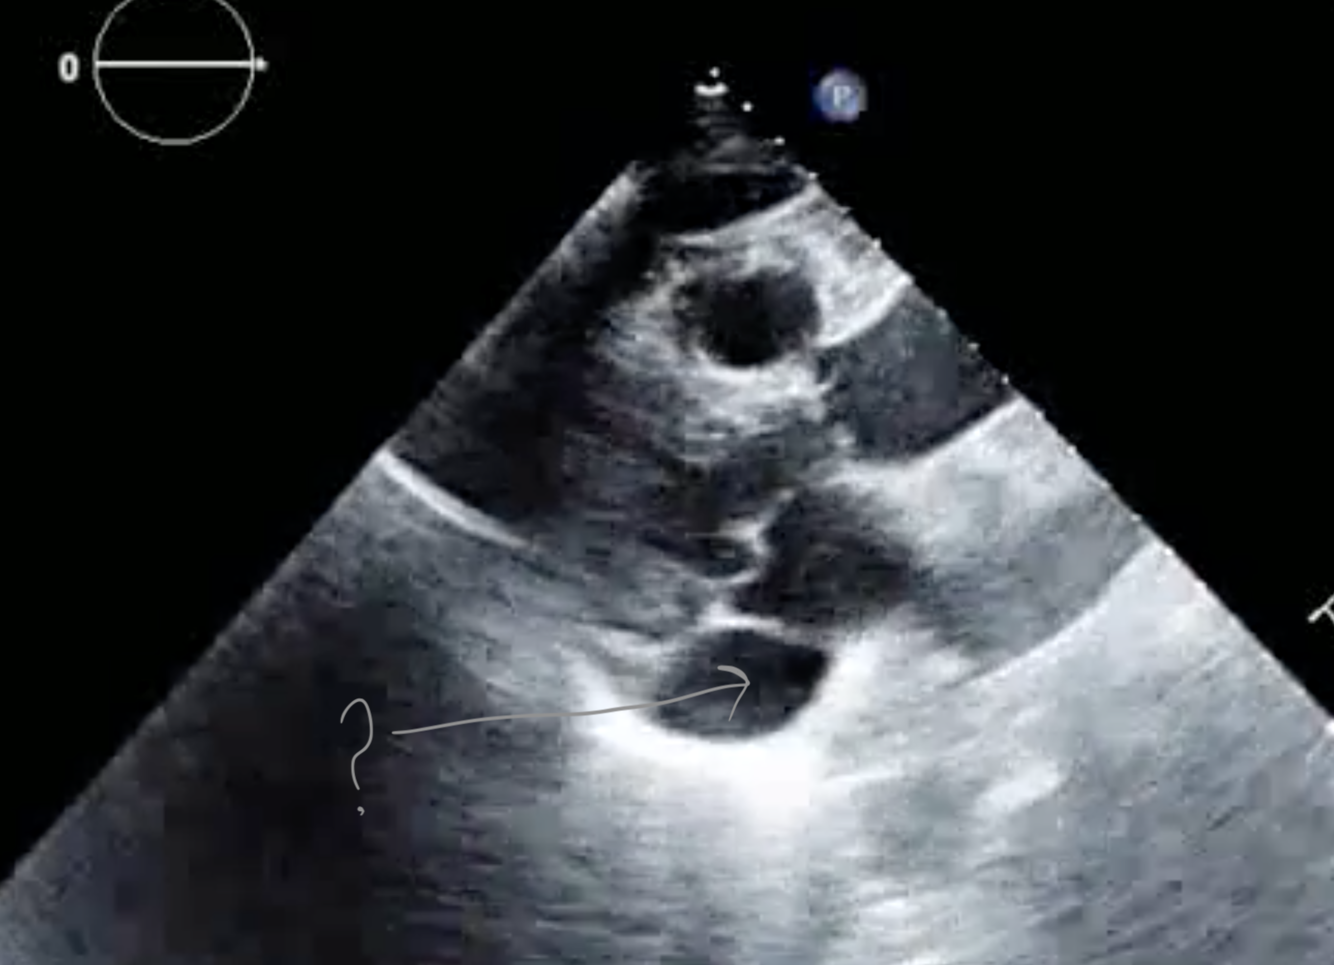

Q

The arrow in the following image is pointing to the:

A

RPA